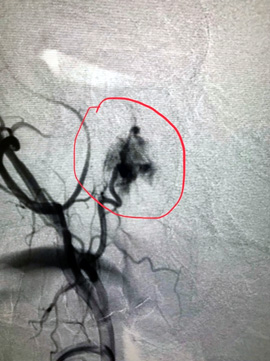

Было принято решение о проведении хирургического вмешательства. С учетом генеза образования первый этап вмешательства выполнили эндоваскулярные хирурги. Ангиография подтвердила сосудистый характер опухоли, помогла определить размеры, распространенность и источники кровоснабжения и определить объем предстоящей операции. Произведена эмболизация образования среднего уха справа с положительным эффектом.

— Через правую лучевую артерию была выполнена катетеризация правой наружной сонной артерии. С помощью ангиографии была выявлена ветвь наружной сонной артерии, питающая опухоль. Микрокатетер был заведен в эту ветвь и подведен непосредственно к опухоли. С помощью эмболизационных частиц размером 700 нм выполнена селективная эмболизация опухоли, что привело к полному прекращению ее кровоснабжения. Катетер был удален, на место пункции наложена повязка. Доступ через лучевую артерию является одним из самых безопасных и не требует строгого соблюдения постельного режима после процедуры, что, несомненно, делает пребывание в стационаре намного комфортнее.